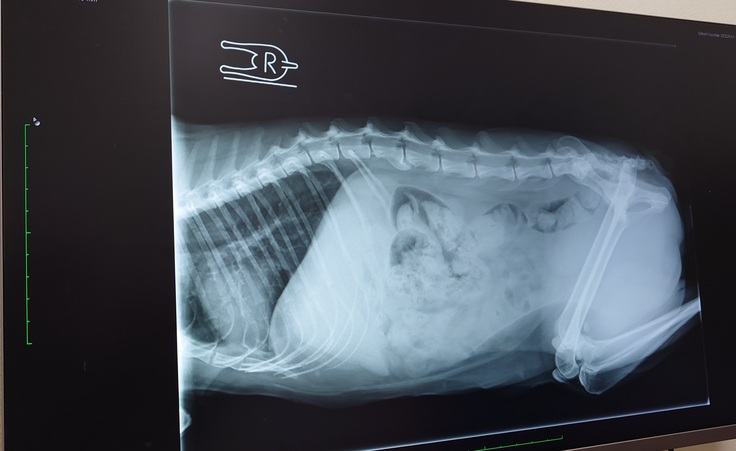

🐈レントゲン検査の結果、背骨に2つ奇形があることが分かりました。うんちの出が悪くて便秘気味になってるのもそれが原因かもとの事でした🐈

うんちもお腹の中にたくさん残ってるんだけど、ヨッちゃんの背骨に奇形が2つあるから、馬尾(ばび)症候群のような症状があって排便する時に痛みや違和感がある等でうまく力めてないのかもしれないということでした。

腎盂腎炎の抗生物質(1日2回で10日分)と便を柔らかくする薬(1日2回で毎日飲み続ける)を処方してもらいそれを飲むことになりました。